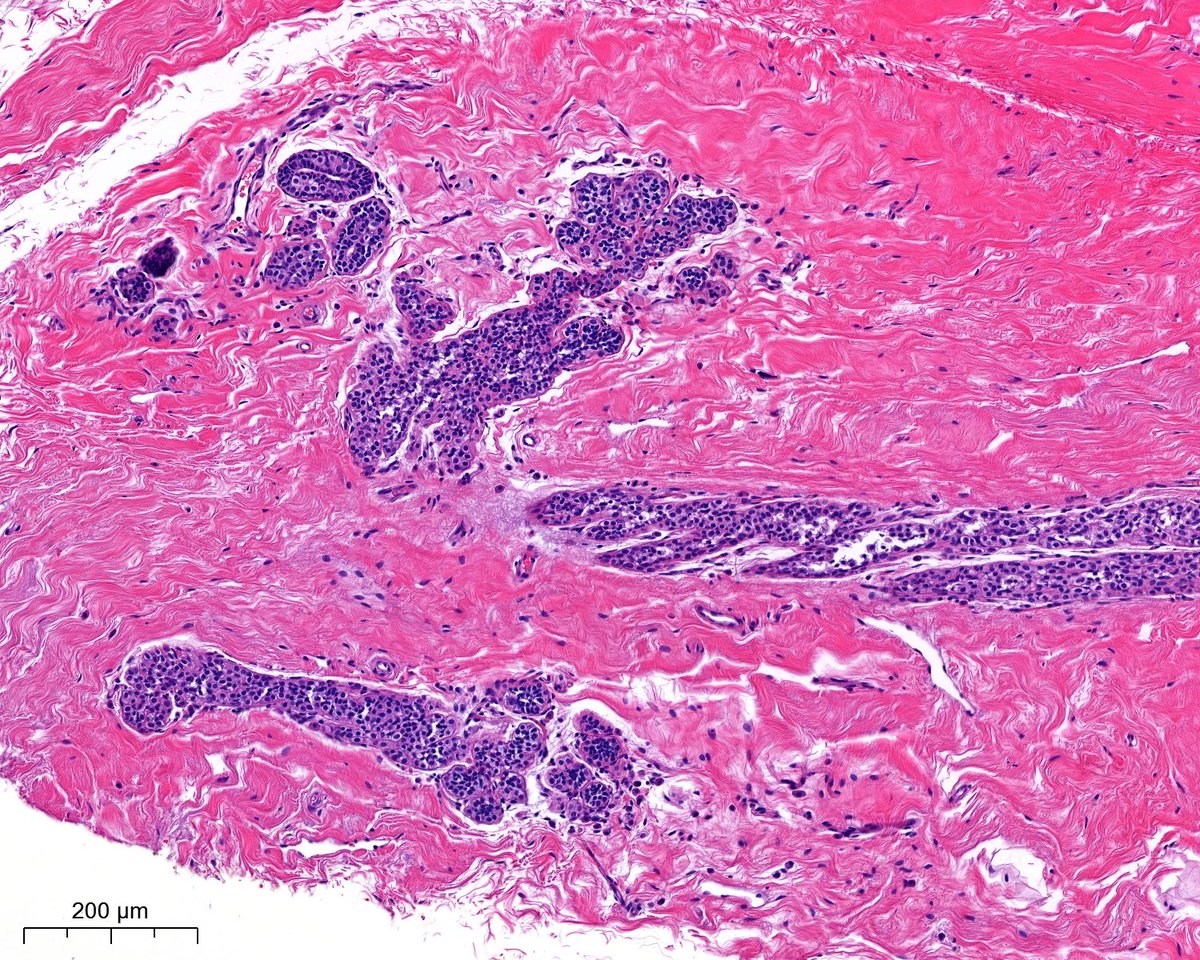

Placental Site Trophoblastic Tumor • RARE malignant trophoblastic neoplasm from intermediate trophoblasts • Mean Age: 31 • 2/3 cases follow full term pregnancy (median latency 12-18 months) • 🩺: Vaginal 🩸, uterine enlargement • ~25-30% may develop recurrent dz